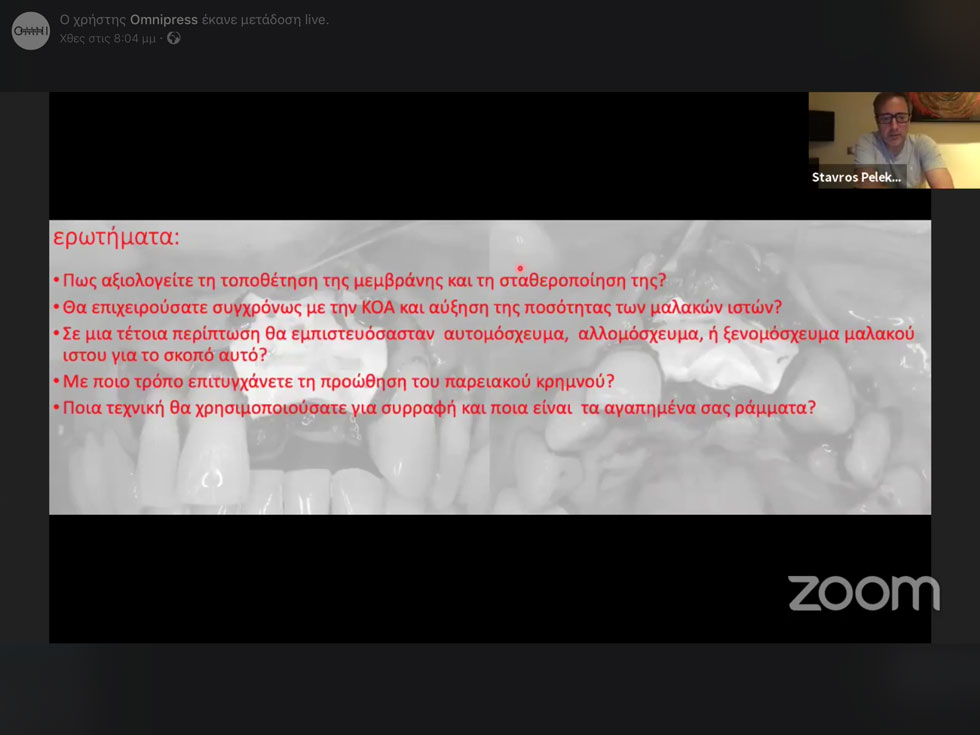

Απαντήσεις που προέκυπταν επιτόπου και μάλιστα όχι από έναν αλλά από τρεις από τους πιο έμπειρους κλινικούς. Οι συμμετέχοντες είχαν την ευκαιρία να στέλνουν τα σχόλια και τις απορίες τους αλλά και να δίνουν τις δικές τους απάντησεις σε μικρές δημοσκόπησεις για το τί θα έπρατταν οι ίδιοι. Στο τέλος αφιερώθηκε χρόνος για να απαντηθούν όλες.